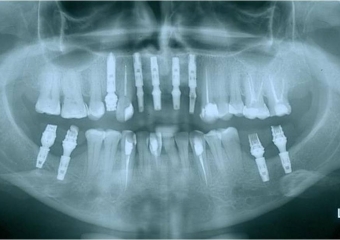

Raio x com próteses provisórias sobre implantes cone morse